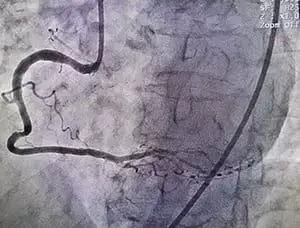

La radiología intervencionista es una especialidad médica dedicada al diagnóstico y tratamiento mediante la realización de procedimientos mínimamente invasivos, guiados por estudios de imágenes diagnósticas. Los radiólogos intervencionistas utilizan su